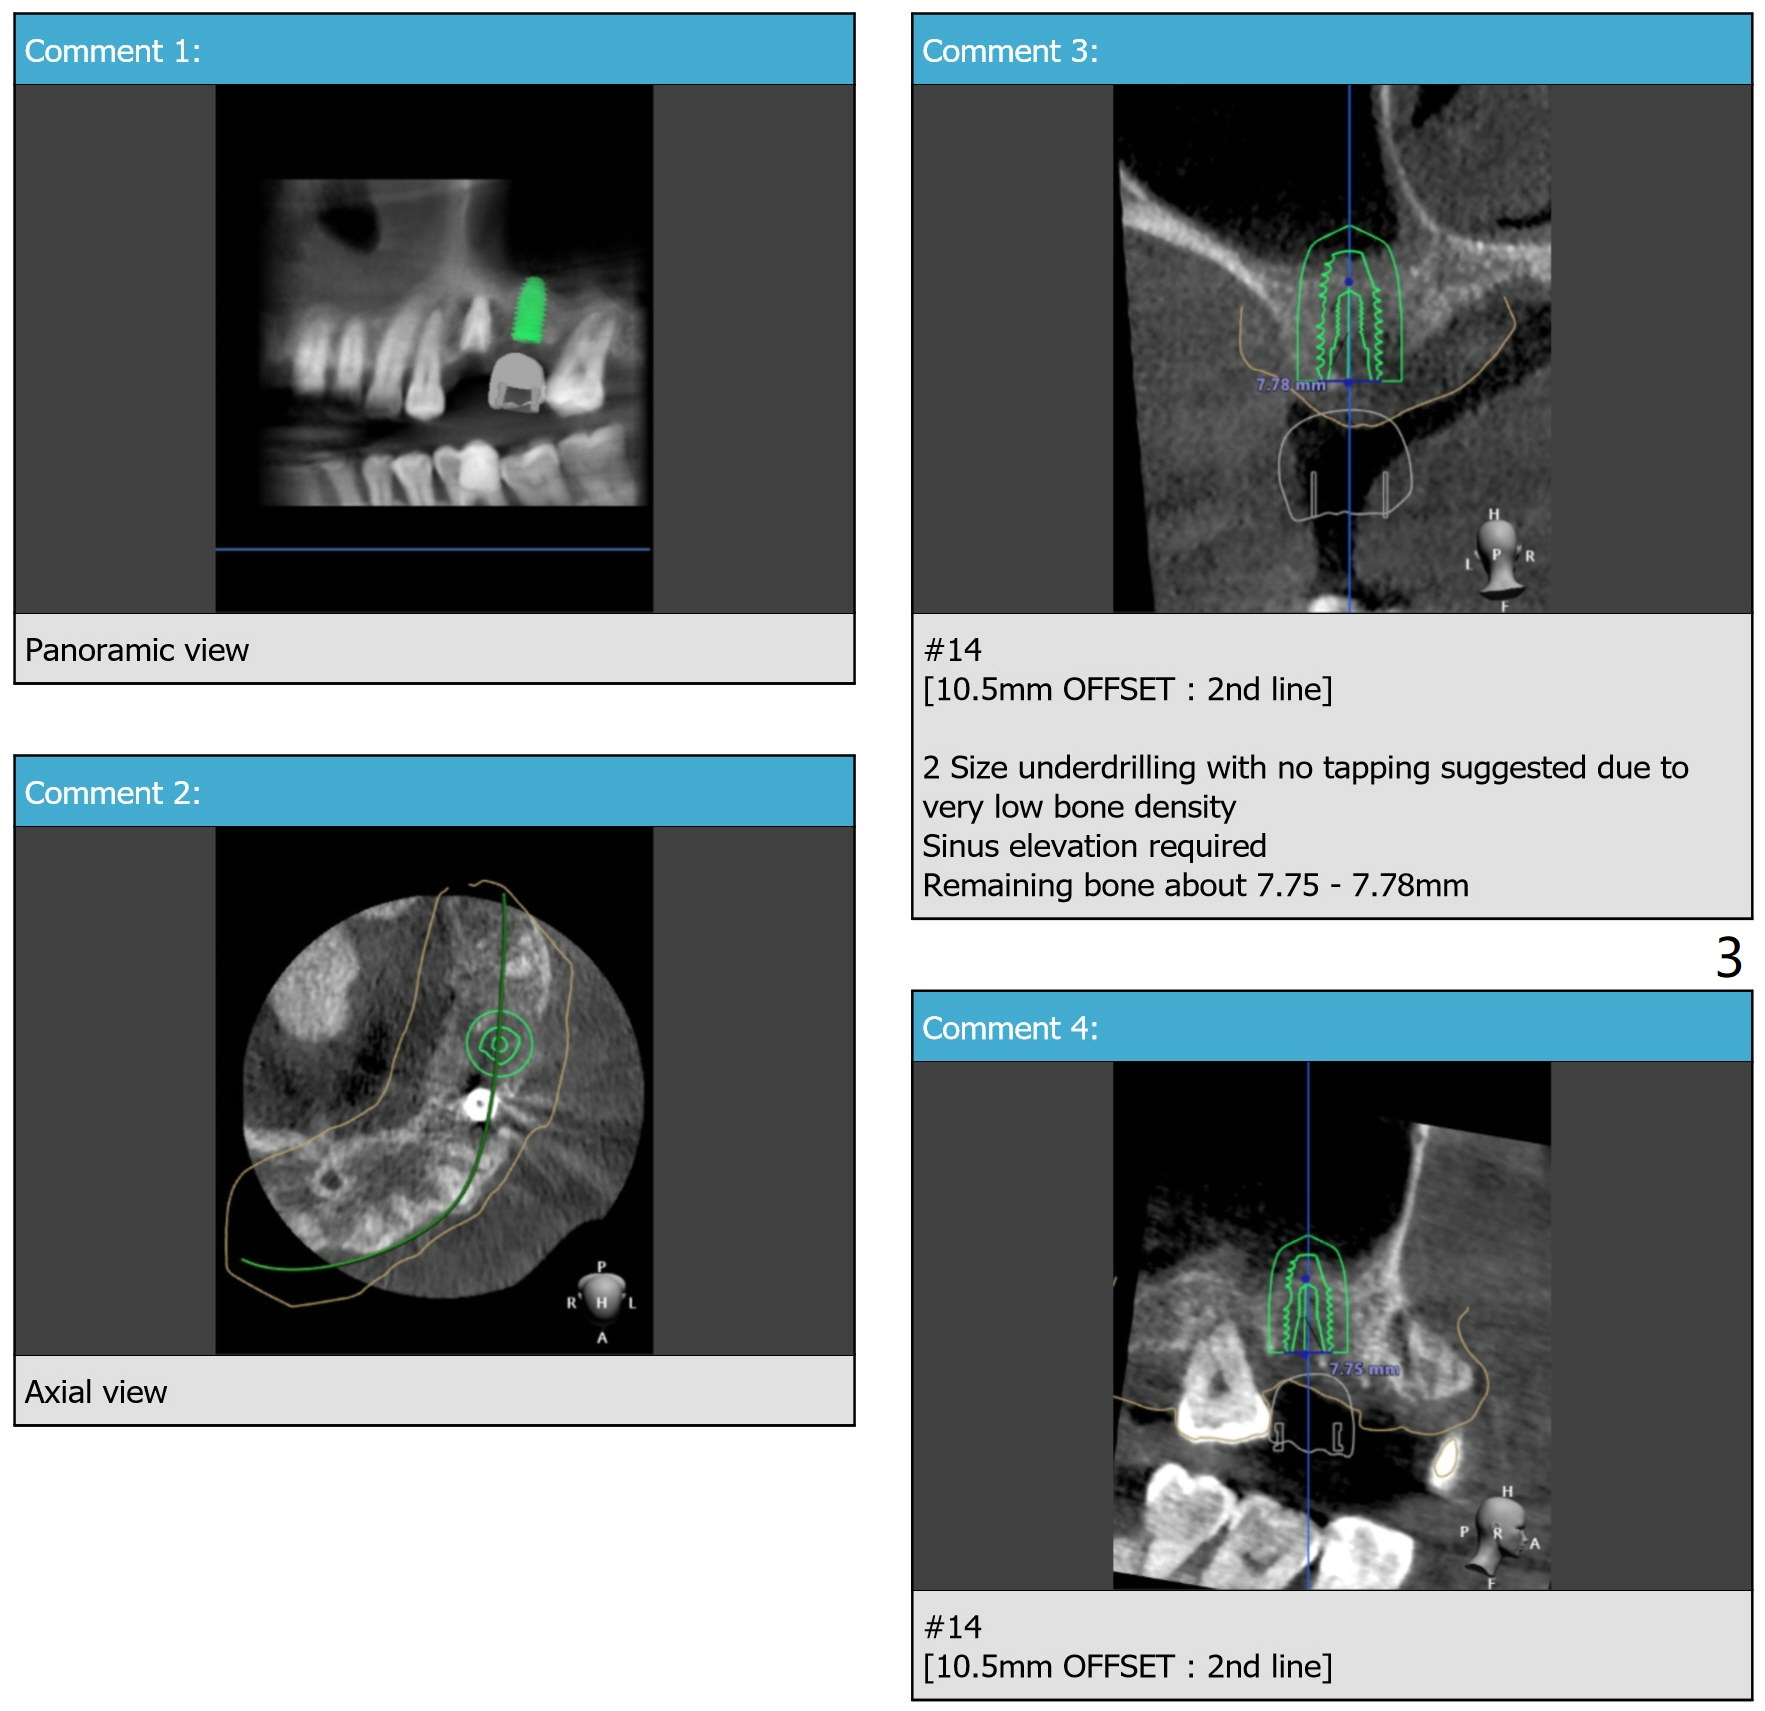

Since bone density is low 3 months post 2nd loss, under drilling, sinus lift for a longer implant (7.3 vs. 10 mm) and PRFx2 are required. One for sinus lift, the other for wound closure (prepare suture). If primary stability is low, no healing abutment is used. Prepare 4 and 4.5x10 dummy implants for sinus lift.